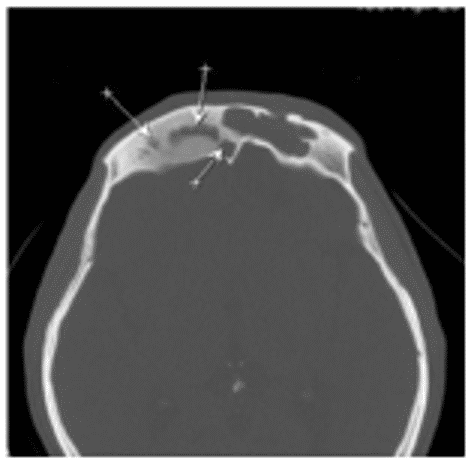

Остеома - КТ позволяет не только выявить наличие остеомы околоносовых пазух, но и определить тип ее строения, установить место исходного роста. Рентгеновская картина остеомы соответствует ее строению. Компактные остеомы - шаровидные, округлые опухоли, имеющие вид плотного, почти бесструктурного новообразования (рисунок 1).

Рис. 1. КТ околоносовых пазух, коронарная (А) и аксиальная (Б) плоскости: Компактная остеома решетчатого лабиринта справа в виде округлого добавочного интенсивного образования с четкими ровными контурами